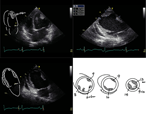

Aortic valve reconstruction with autologous pericardium in a patient with osteogenesis imperfecta

A Ümit Güllü and others

Journal of Surgical Case Reports, Volume 2018, Issue 10, October 2018, rjy251, https://doi.org/10.1093/jscr/rjy251